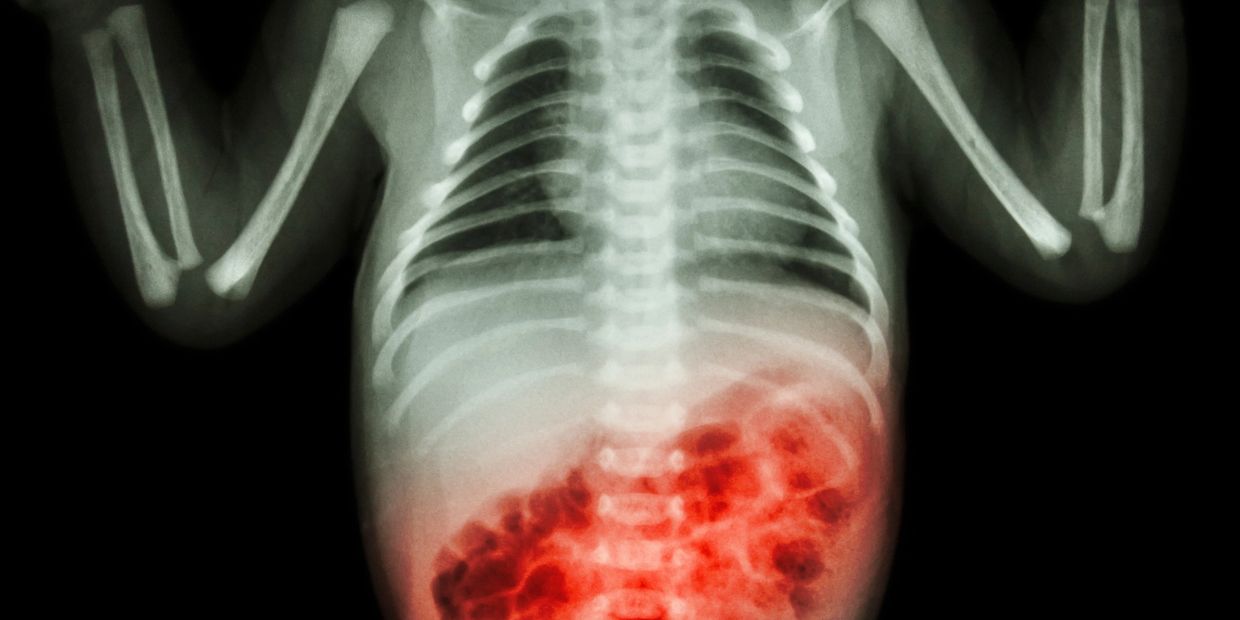

Necrotizing Enterocolitis

What Is NEC?

Necrotizing enterocolitis (NEC) is a serious gastrointestinal disease that primarily affects premature infants, causing inflammation and damage to the intestine. The term "necrotizing" refers to the death of tissue, "entero" to the intestine, and "colitis" to inflammation of the colon. NEC is characterized by the inflammation and eventual death of intestinal tissue, potentially leading to complications like intestinal perforation, infection, and even death.

• Diagnosis: Diagnosis often involves abdominal X-rays, which can reveal gas or air bubbles in the intestinal wall or abdominal cavity.